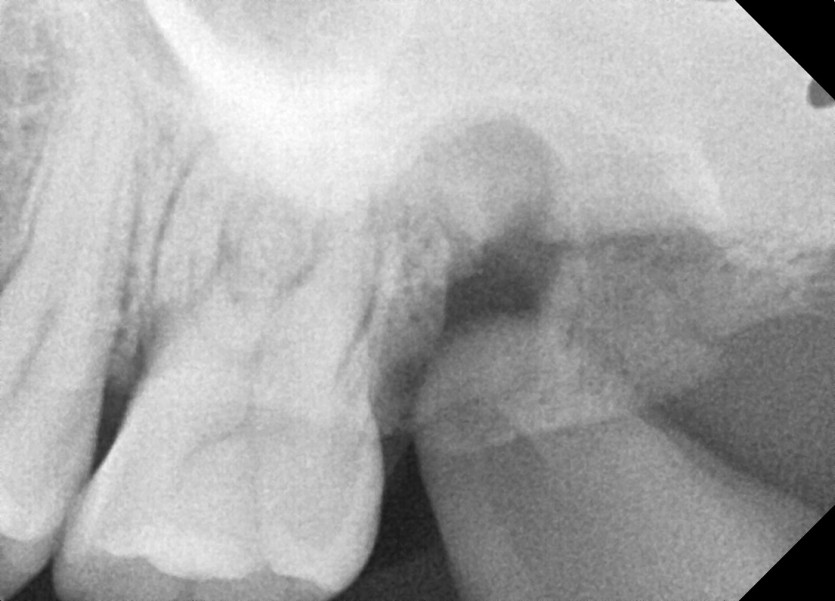

#38 사랑니 발치 (#27,37포함)

구강 외과 전문의가 당일 발치했습니다.